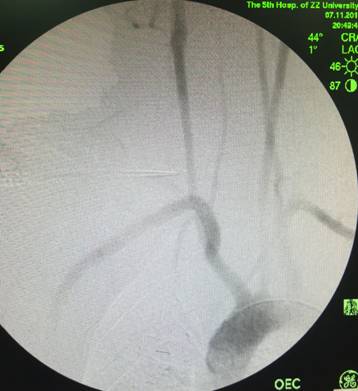

接下来的处理就水到渠成,准确定位后置入1枚覆膜支架,完全覆盖破口,并保留右侧椎动脉,防止患者术后出现后循环缺血症状。再次造影(图4),未见造影剂渗出,取出填塞纱布后未再见活动性出血,手术效果立竿见影,由于为污染性伤口,崔文军副主任又充分清洗伤口,再次确认没有出血后仔细缝合伤口。术后经过重症监护室医护人员的精心护理,患者顺利拔管,在返回普通病房后施敏护士长及主管护士格外细心的照顾,目前患者病情已稳定,不日即将出院,与家人重圆幸福生活。

▲ 图4